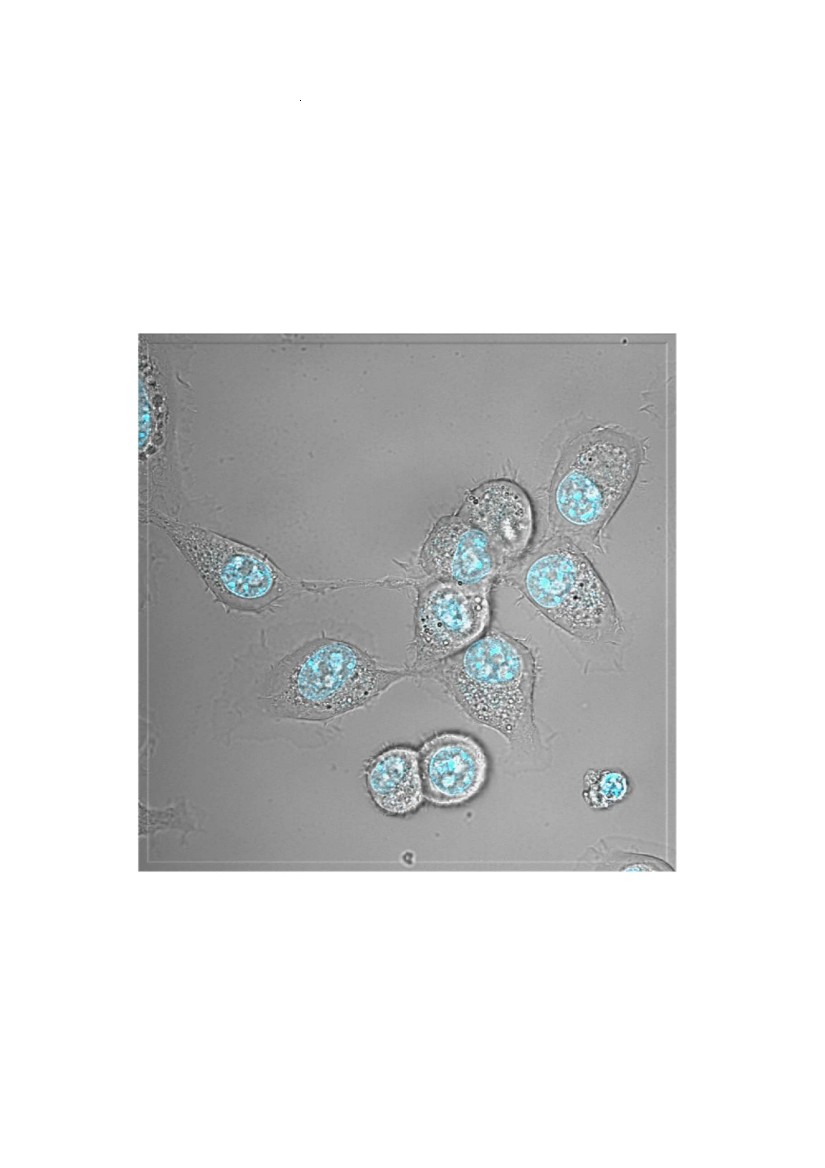

CT26 mixed with 293GL CT26 mixed with 293GL-PS2 A549 mixed with 293GL-PS2 PS2 induces bystander “fritolysis”